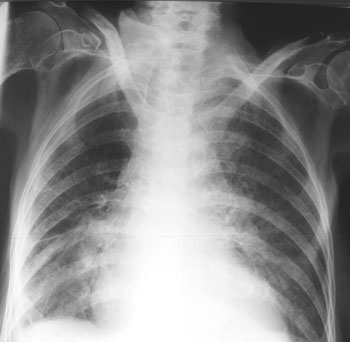

Eine 76-jährige, noch rüstige Patientin beklagt stark zunehmende Atemnot seit zwei Tagen. Zusätzlich hat sie Husten mit manchmal bräunlich-gelblichem Auswurf. Subfebrile Temperaturen. Thorakale Schmerzen werden verneint.

Sie ist wegen einer arteriellen Hypertonie mit einer Zweierkombination behandelt und leidet unter einem Diabetes mellitus Typ 2. In der Anamnese berichtet die Patientin ausserdem über eine Tuberkulose in der Kindheit.

Bei der Untersuchung fällt die Kurzatmigkeit der Patientin sofort auf. Basal beidseits finden sich feuchte Rasselgeräusche. Eine Röntgenaufnahme ist nur liegend möglich.

Thorax pa